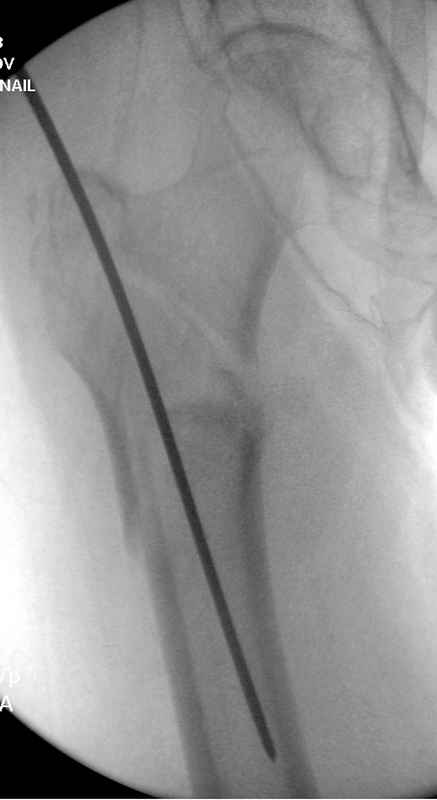

По нашему мнению линия перелома проходит вверху через латеральный отдел шейки бедра, вертельная область состоит из нескольких фрагментов. В таких условиях применить DHS или дистальную бедренную пластину LCP представляется нам сомнительным. Закрытый остеосинтез проксимальным гамма-гвоздем или PFNa невозможен т.к. нет ЭОПа.

Возможно открытый остеосинтез гвоздем PFNa?

Прилагаю Р-ы на вытяжении.